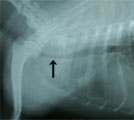

初診時胸部X線所見。胸部気管前部の扁平化およびLB1に結節影あり。 初診時気管支鏡所見。胸部気管前部に気管虚脱(GradeIII)あり。 第21病日。ステント設置後のX線所見。気管は拡張した。食道チューブあり。 第116病日の気管支鏡所見。肉芽形成・菌コロニーなし。固定糸がみえる。

経過:初診時、身体検査にて発熱なく、元気なく、飲水時誤燕あり。CBCおよび生化学で白血球数24000/μl、BUN 80.0 mg/dlと上昇、胸部X線所見で胸部気管前部が扁平化およびLB1に結節影あり、血液ガス分析ではpHa 7.415, Paco2 34.1 mm Hg, Pao2 91.5 mm Hgで正常。第6病日の気管支鏡検査にて頚部気管後部から胸部気管前部にかけ気管虚脱みられ、GradeIIIと診断した。LB1のブラシ生検では有意な細菌は検出されず、細胞診でも炎症・腫瘍なかった。飲水困難を伴った胸部気管虚脱GradeIIIと臨床診断した。内科治療を始めたがやはり飲水ごとに強くむせる症状あり脱水症状が生じた。第21病日、シリコン製の気道ステントを作成し設置した。同時に食道造瘻チューブを設置した。その後、内科療法(抗生剤、去痰剤、気管支拡張剤、ステロイド間欠投与)、ネブライゼーション、径チューブ輸液を行い、口からの飲水を制限した。術後、軽い乾咳が残るも苦しそうな状況は全くなくなり全身状態は改善した。1ヶ月後、自宅でネブライザーと径チューブ輸液を中心とした治療を行い咳症状はさら軽快した。第90病日、第116病日に気管支鏡検査にて経過観察を行ったが、ステント内に肉芽形成・菌コロニーの形成なかった。現在、約1年が経過しているが間欠的に自宅療法を行うだけでほぼ支障なく通常の生活をしている。